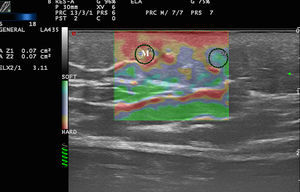

In a study by Bhatia et al.,22 52 non-nodal neck masses were evaluated using real-time qualitative ultrasound elastography. The diagnosis of the lesions was later corroborated by cytology and histology. The lesions were evaluated semiquantitatively on a scale of 0 to 3, where 0 was completely soft and 3 was completely stiff. Lipomas were less stiff than other types of lesions, most of which were cysts, malformations, and neurogenic tumors (Fig. 4). In an extension of the study, SWE was used to assess malignant and benign neck tumors.23 The mean stiffness of the malignant tumors (226.4kPa) was higher than that of the benign lesions (28.3kPa) and the difference was statistically significant. With a cut-off of 174.4kPa, sensitivity of 83.3% and specificity of 97.5% were achieved in the differentiation of benign and malignant lesions. The authors noted that all tumors were correctly diagnosed with conventional ultrasound and that elastography would not have altered the treatment, but they argued that less experienced operators could find the technique helpful in the diagnosis of neck lesions.

Park et al.24 used elastography to differentiate inflamed and unruptured epidermal cysts (Fig. 4, B), the latter being stiffer than the former.